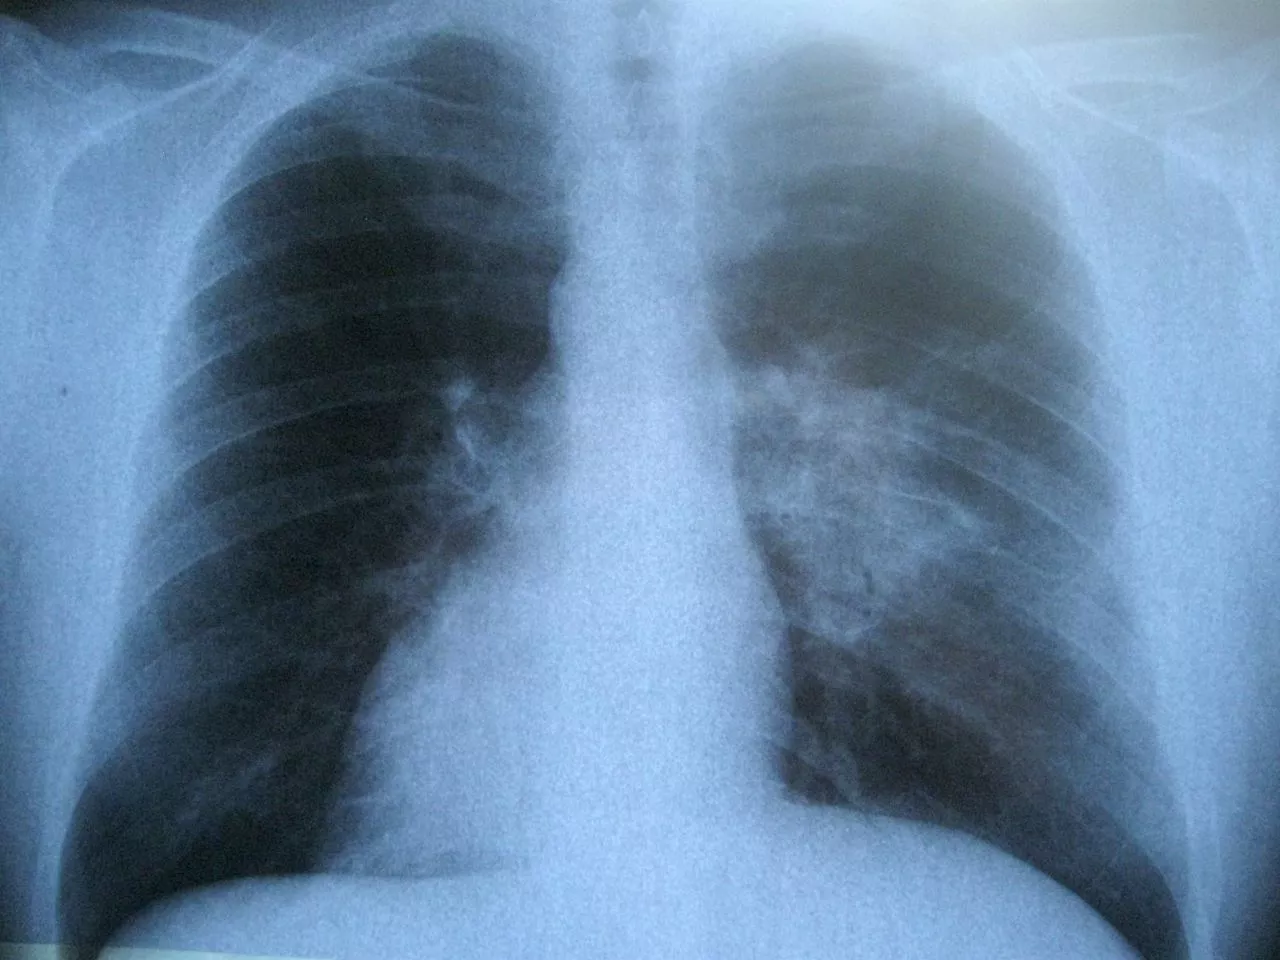

A tüdőrák tünete lehet újonnan jelentkező köhögés, véres köpet a köhögés után, légszomj, mellkasi fájdalom. Később, a betegség előrehaladtával más tünetek is jelentkezhetnek, így pl. fogyás, fáradtság, elhúzódó tüdőgyulladás, fájdalom a test más részeiben, vérszegénység. A tünetek bármelyikének előfordulásakor haladéktalanul orvoshoz kell fordulni. Általában a háziorvoshoz kerülnek a tüdőrákra utaló tünetekkel a betegek, és gyanú esetén a háziorvos utalja őket szakorvoshoz, ahol további vizsgálatokkal – pl. MRI, szövettani vizsgálat – állapítják meg, hogy az adott beteg esetében tüdőrákról van-e szó.